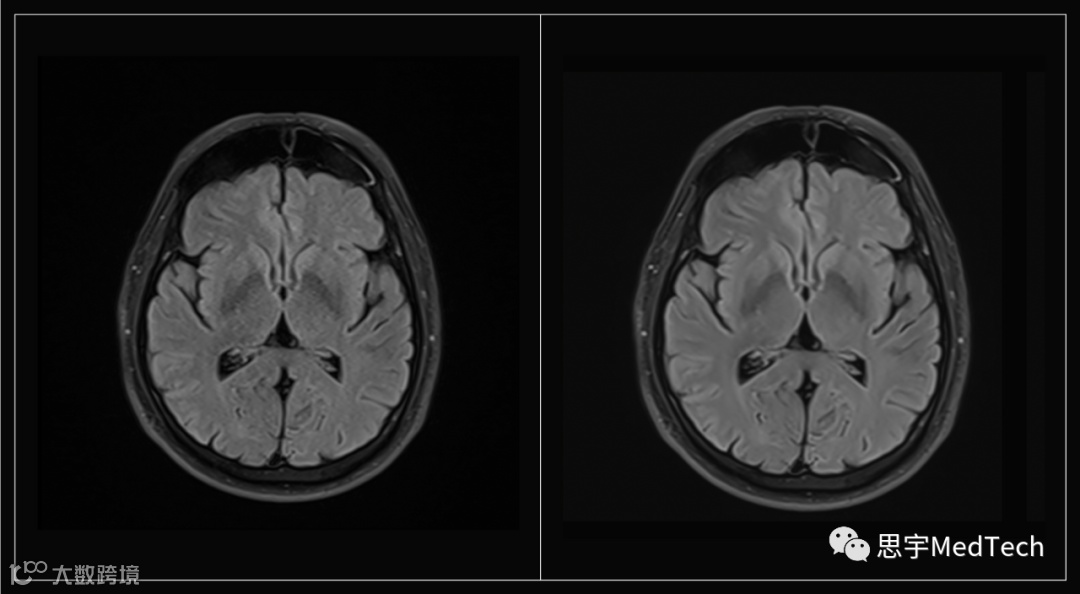

为了测试该技术,该公司创建了一种快速MRI协议(protocol),该协议会产生嘈杂的图像,而新的AI系统能够提高图像的质量。

▲(图左为未使用AI技术形成的MRI图像,图右为Ezra Flash AI增强后图像)

据悉,Ezra使用其专有的纵向MRI数据集来训练AI,该数据集包括数十万张患者和健康受试者的MRI图像。

Ezra还训练AI评估哪些元素对于生成完整和准确的图像是必不可少的。这使得Ezra能够在高速MRI扫描中提高图像质量,这些扫描已经达到了当前护理标准的极限 。